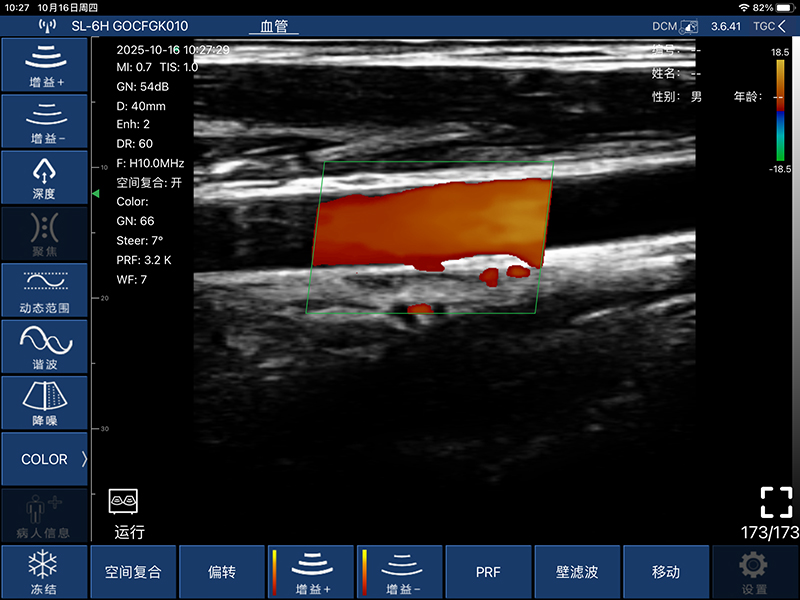

• 显示模式:B、B/M、Color、PW、PDI

• 扫描方式:电子阵列扫描

• 探头频率:7.5/10MHz

• 扫描深度:20-100mm,可调